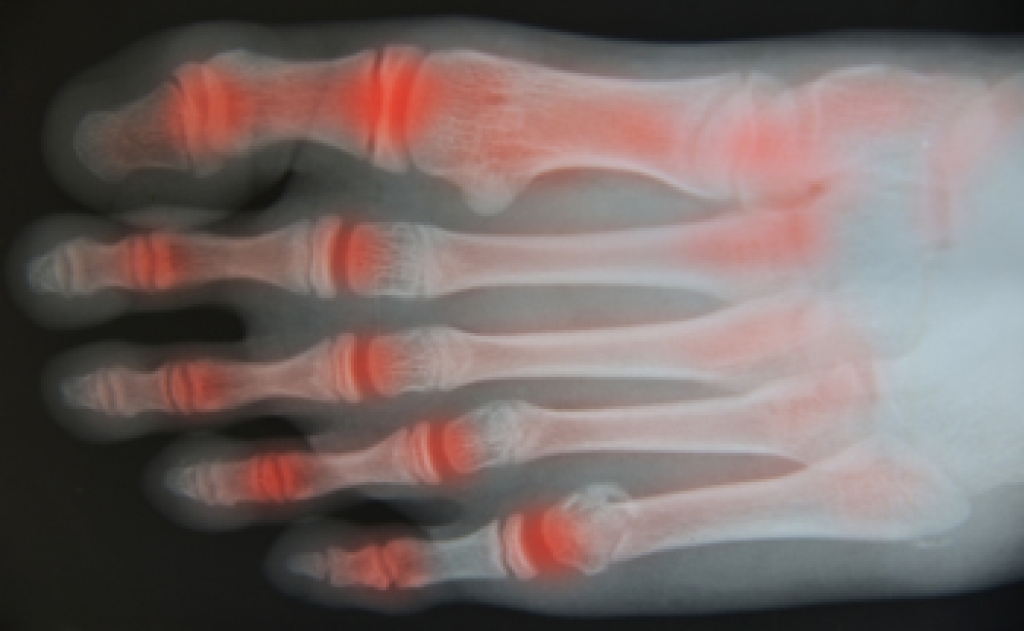

Tarsal Tunnel Syndrome and Rheumatoid Arthritis

Rheumatoid arthritis (RA) is an autoimmune disease in which the body’s immune system attacks the otherwise healthy cells that make up the linings of joints. Because each foot contains 33 joints, the feet, as well as the ankles, are often affected. RA can make other foot and ankle conditions more likely to occur. One such condition is tarsal tunnel syndrome, in which the posterior tibial nerve is compressed or damaged, causing burning pain, numbness, and tingling in the affected foot. Tarsal tunnel syndrome is frequently seen in people with RA. If you have RA, it is suggested that you be under the care of a podiatrist who can monitor the health of your feet and treat any problems as they arise.

Because RA affects more than just your joints, including the joints in your feet and ankles, it is important to seek early diagnosis from your podiatrist if you feel like the pain in your feet might be caused by RA. For more information, contact one of our podiatrists of Pennsylvania Foot & Ankle. Our doctors will assist you with all of your podiatric concerns.

What Is Rheumatoid Arthritis?

Rheumatoid Arthritis (RA) is an autoimmune disorder in which the body’s own immune system attacks the membranes surrounding the joints. Inflammation of the lining and eventually the destruction of the joint’s cartilage and bone occur, causing severe pain and immobility.

Rheumatoid Arthritis of the Feet

Although RA usually attacks multiple bones and joints throughout the entire body, almost 90 percent of cases result in pain in the foot or ankle area.

Symptoms

• Swelling and pain in the feet

• Stiffness in the feet

• Pain on the ball or sole of feet

• Joint shift and deformation

Diagnosis

Quick diagnosis of RA in the feet is important so that the podiatrist can treat the area effectively. Your doctor will ask you about your medical history, occupation, and lifestyle to determine the origin of the condition. Rheumatoid Factor tests help to determine if someone is affected by the disease.

If you have any questions, please feel free to contact one of our offices located in Bensalem, Philadelphia, Northeast Philadelphia, Yardley, PA, and Hamilton, NJ . We offer the newest diagnostic and treatment technologies for all your foot care needs.

Read more about Rheumatoid Arthritis in the Feet